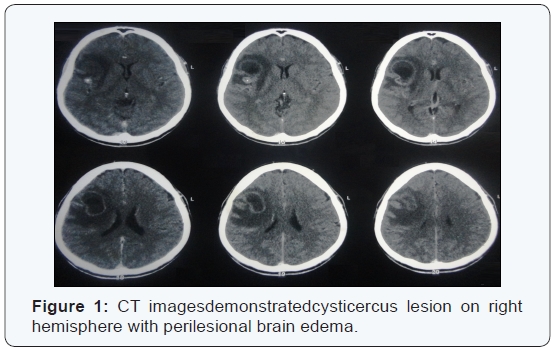

Cysticercosis is the most common parasitic disease worldwide; with an estimated prevalence greater than 50 million persons are infected. The life cycle of the pork tapeworm, Taenia solium, begins at the larval stage in pigs. Human tapeworm infection occurs when T. solium cysts are ingested from undercooked pork. The larvae attach to the human gut and grow into adult tapeworms. The adult tapeworm then sheds proglottids into human feces that can contaminate the pig food supply. Eggs ingested by pigs develop into the larval stage, travel through the intestinal wall, enter the bloodstream, lodge in various pig tissues, and develop into cysts. When humans ingest eggs, through fecal-oral transmission, they become dead-end hosts of the larval stage of the parasite and develop cysticercosis similar to pigs. This parasite is a leading cause of seizures and epilepsy in the developing world that is caused by infection with Taenia solium. CASE: 55-year-old man presented with a 14-day history of left lower limb numbness, unsteadiness of gait. On neurological examination, he had left lower weakness (strength, 4/5), with normal tone and deep-tendon reflexes. The plantar reflexes were normal bilaterally. Brain CT documented the presence of cystic lesions in the right frontal lobe associated with cerebral. The radiological data revealed a solitary lesion highly suggestive of high-grade glioma (Figure 1). He received a diagnosis of glioma and treated with surgical treatment. During surgical procedure were found multiples cysts containing yellowish material compatible with neurocysticercosis (Figure 2). The anatomopathological study confirmed the diagnosis of neurocysticercosis [1].